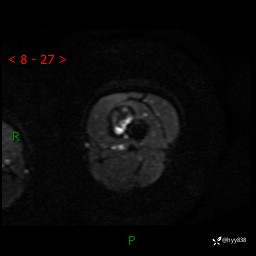

左大腿MRI平扫+增强